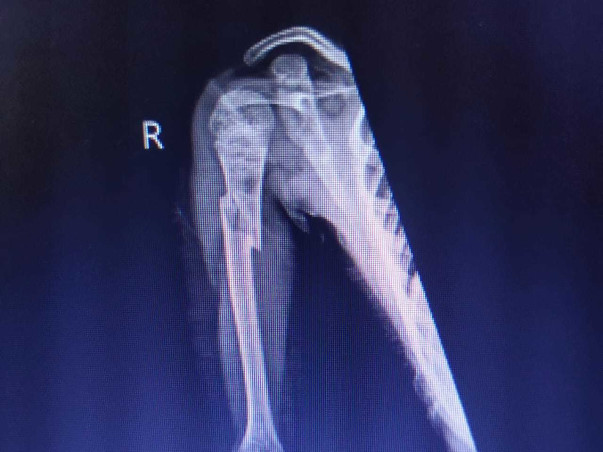

To make a living, I work as a coach. Sanjay is suffering from Osteogenesis Imperfecta by birth.

He is receiving medication at Christian Medical College but has not yet been admitted. Until now, we've spent about Rs. 300000.